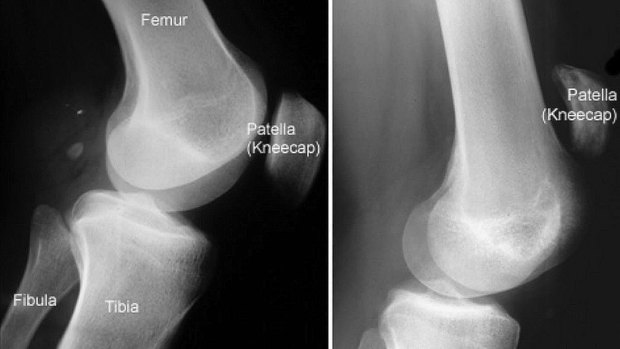

‘A partial patellar tendon tear is typically treated with immobilization for up to six weeks, knee braces, and physical therapy. A complete tear or rupture, or a partial tear that doesn't heal well, will require surgery.’

Kurtley Beale did his Patella (Torn clean off the Bone- see x-rays below - Left is normal and Right is Beale's Torn Patella ) - I think he was out for 6 months or so ? - The NRL Physio say's recovery time is 6 to 9 months when surgery is required